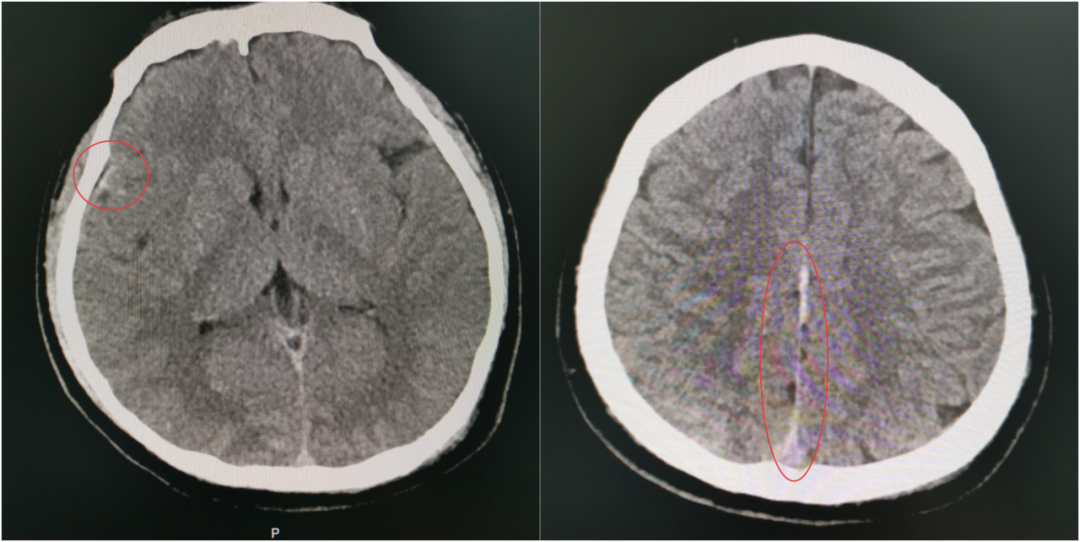

当第二次 CT 提示出现硬膜外血肿、蛛网膜下腔出血范围进一步扩大时,虽然符合预判,但每个人都清楚:出血量和点位的不可控,血肿扩大可能压迫脑组织,任何微小变化都可能改写结局,之前的一系列努力可能功亏一篑。

伤情再次变化,出血范围扩大

这一“激战”持续到次日清晨8点,于如同教授亲自到ICU查房,他仔细审阅了所有的检查和监护数据后,欣慰地确认:“颅内情况稳定了,出血控制得很好,暂时不需要手术。接下来,继续在ICU密切观察,精心护理,帮助他稳定恢复。”

于如同教授现场查房、评估